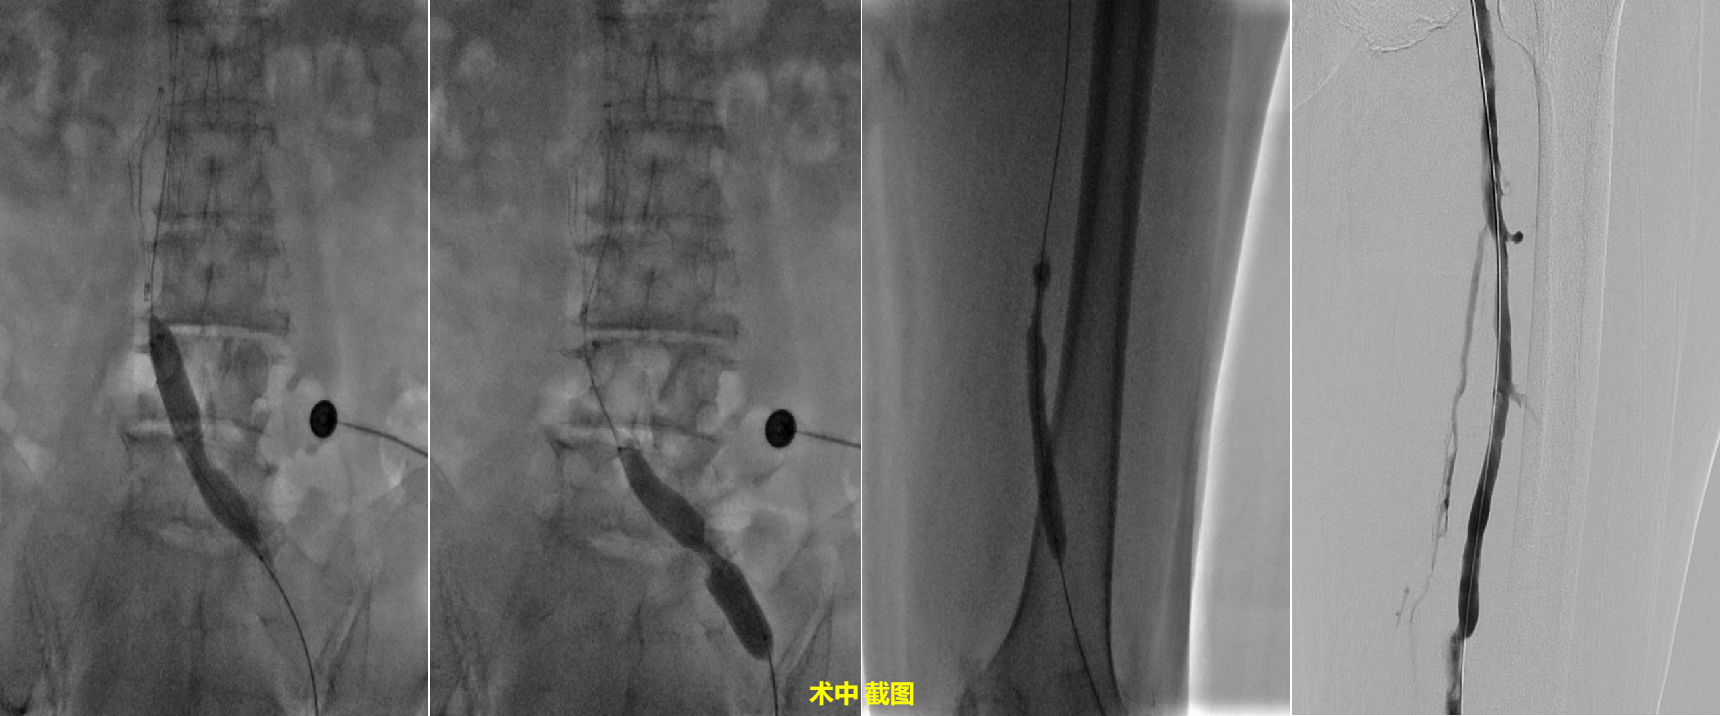

第2台手术:左髂总静脉闭塞,左髂静脉至左股静脉段侧支循环丰富,左侧股静脉至腘静脉段狭窄65%,侧支循环丰富,考虑左下肢静脉存在大量血栓,手术行下腔静脉滤器置入术+静脉内球囊扩张术+置管溶栓术,手术顺利开通左下肢髂静脉至腘静脉段。

第2例患者为69岁,女性, 双下肢肿痛1月余,双下肢水肿,以膝关节以下凹陷性水肿为主,左侧明显,伴有胀痛感,入住我科后诊断为左髂静脉栓塞。充分完善术前准备后,再局麻下行经皮选择性静脉造影术(双下肢)+经皮选择性静脉造影术(下腔静脉)+经皮静脉内滤网置入术+经皮静脉内球囊扩张术(左髂、股静脉)+经皮静脉内置管溶栓术,造影术中左腘静脉造影显示:左髂总静脉闭塞,左髂静脉至左股静脉段侧支循环丰富,左侧股静脉至腘静脉段狭窄65%,侧支循环丰富,考虑左下肢静脉存在大量血栓。术中行下腔静脉滤器置入术+左下肢静脉球囊扩张术+置管溶栓术。术毕,患者左下肢静脉血流恢复通畅,侧支循环基本消失。